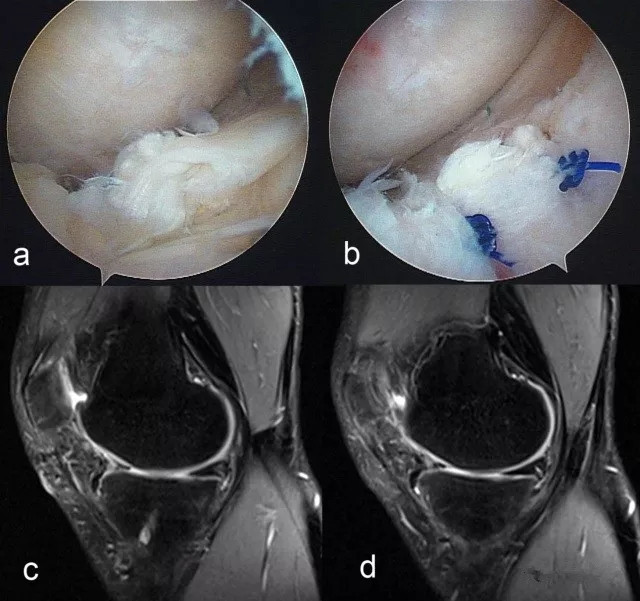

本书通过丰富的病例和大量精美的图片将现代成熟的诊断和治疗方法全面详实的呈现给读者,是一部系统的、专门阐述半月板外科技术的教科书。通过将笔者丰富的实践经验与读者分享,使更多从事运动医学和关节镜外科专业的骨科医师能进行完整的学习和系统提高。

本书围绕临床诊断和治疗进行了系统详细的介绍,突出其实用性:包括经典的自内向外和自外向内缝合技术、快捷易行的半月板固定物、精细的全内缝合钩缝合技术和半月板移植手术等,将"基础、经典和提高" 融于一体,对运动医学与关节镜专科医生、骨科住院医生和专科进修医生有非常大的帮助。

海量图片/先睹为快